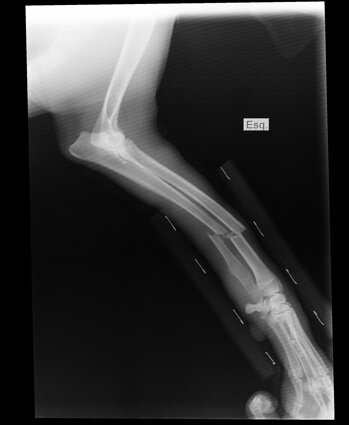

Ortopedia

Visite specialistiche:

Le visite specialistiche sono necessarie quando serve un approfondimento diagnostico in qualsiasi caso clinico complesso. In queste caso è fissato un appuntamento con un medico veterinario che si ocupa soltanto di quella branca.

Visita di controllo della crescita: Durante queste visite, il veterinario valuta la crescita del cucciolo, il suo peso, lo stato di dentizione e la sua condizione fisica generale. Questo aiuta a individuare precocemente eventuali anomalie ortopediche o di altro tipo.